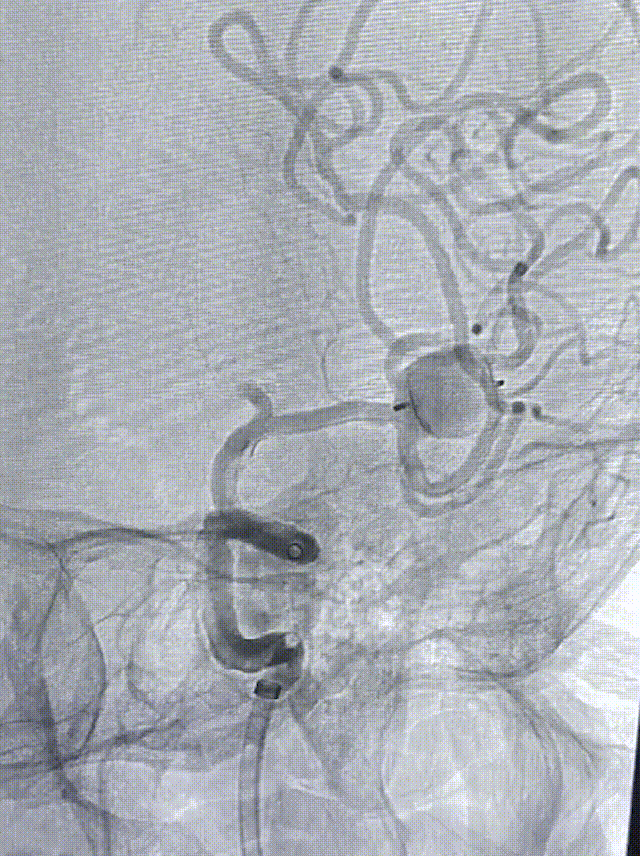

首先将infinity长鞘用0.35泥鳅导丝送至颈内动脉岩谷段及5F-115中间导管输送至海绵窦段下,因VIA™ 33微导管比较硬,遂采用Synchro导丝加SL-10微导管导引下将VIA™微导管送至动脉瘤开口,瘤体三分之一处。体外检查扰流装置无异常后,将其输送至输送导管头端,再次造影,以防VIA™微导管及WEB™输送到位过程路途移位。始终保持VIA™微导管头端位于瘤颈开口内四分之一深度,缓慢推送WEB™至出芽-开花,在此过程中反复微调导管张力,以防导管前窜刺破瘤顶。最后将扰流装置完全打开,再次造影确认瘤颈覆盖效果满意,并可见瘤顶及子瘤不再有造影剂充盈,扰流效果满意。然后保持输送导丝及输送导管张力,将输送导管头端回撤至距解脱点2毫米处,解脱器多次电解后,确认解脱完全,将输送系统撤除,再次造影确认扰流装置覆盖效果满意,大脑中动脉2个分支完整保留。

术后: